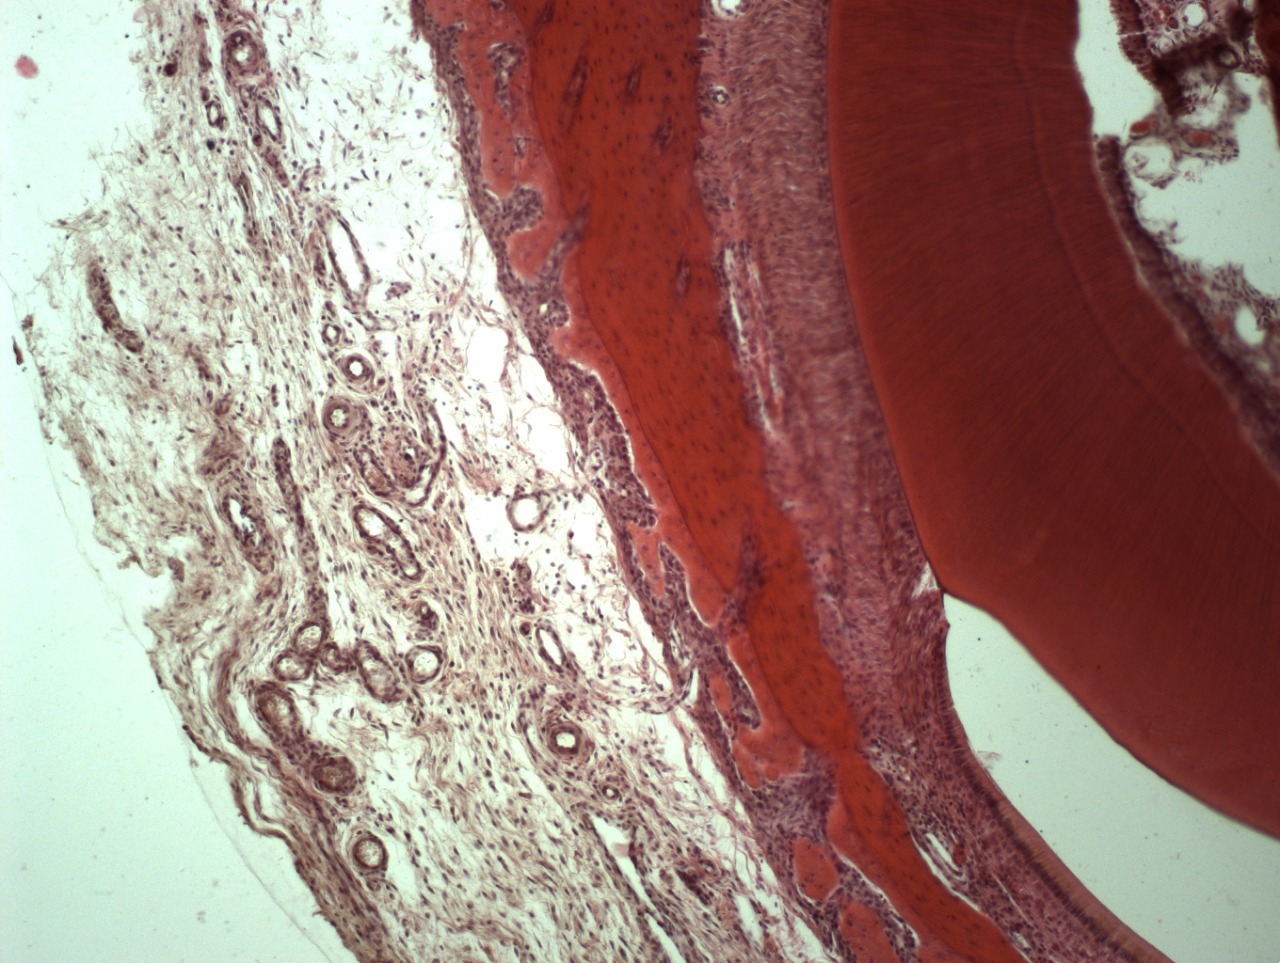

• Например, таким образом удаляются все следы жира, белка, нуклеиновых кислот, мертвых клеток и их компонентов, неколлагеновых белков и прочих соединений. Вследствие такой очистки остается только коллагено-минеральный каркас мертвого межклеточного вещества костной ткани, состав которого стабилен на протяжении всей жизни человека.

• Минерализованную губчатую или кортикальную кость применяют там, где нужно сохранить объем по высоте и ширине, например, при операции поднятия верхнечелюстного синуса или операции имплантации зубов.

• Деминерализованную кость применяют дополнительно для восстановления внутренних костных дефектов: через нее лучше растут кровеносные сосуды, так как она содержит морфогенетический белок (МГБ), но за счет отсутствия минерального каркаса не способна удержать трехмерный объем.